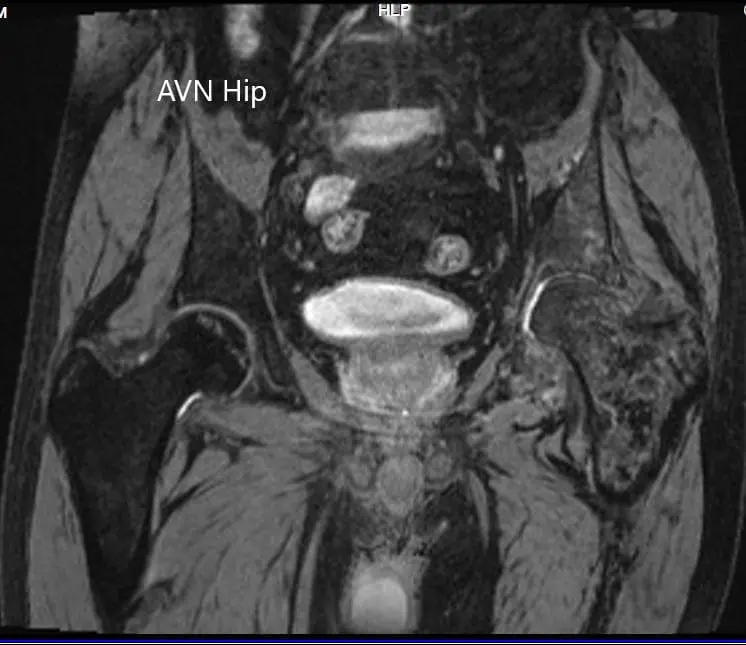

An MRI of the pelvis was obtained which suggested decreased signal intensity on both T1WI and T2WI suggesting sclerosis and periarticular edema. There was a collapse of the head of the femur. The features were suggestive of advanced avascular necrosis of the left hip joint.

MRI showing the T2WI of the pelvis

CMRI showing the T2WI of the pelvis